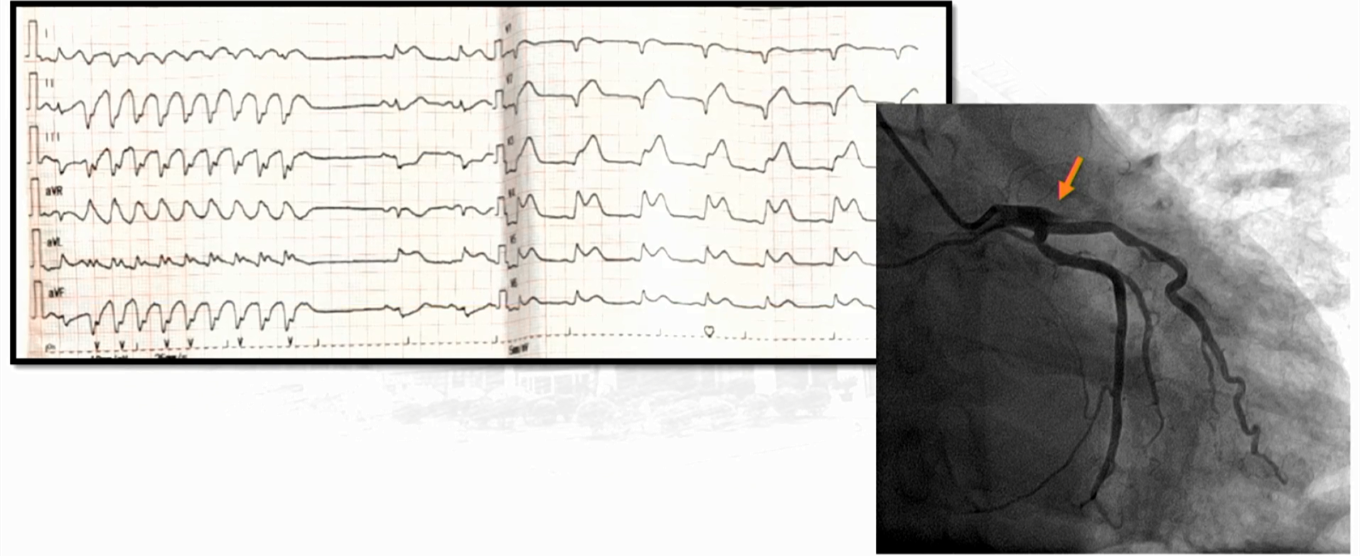

高龄急性广泛前壁,高侧壁心肌梗死急诊pci一例

急性广泛前壁心肌梗死(v